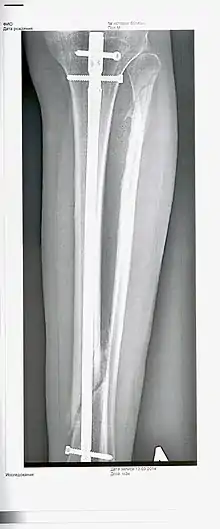

L'immobilisation correcte d'une fracture, par pose d'un plâtre, d'une résine ou de broches, permet au cal de se développer normalement dans des délais propres à chacun des os. Si la consolidation ne respecte pas l'anatomie initiale de l'os, on parle de cal vicieux. Lorsque le cal osseux ne se développe pas ou se développe mal, on aboutit à une pseudarthrose (formation d'une nouvelle articulation, anormale, due à l'absence totale et définitive de consolidation osseuse)[2].